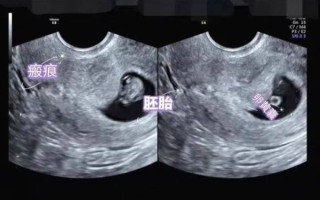

孕妇做b超需要空腹吗_孕早期b超注意事项 不需要空腹,但孕早期经腹B超建议憋尿;孕中晚期通常无需憋尿也无需空腹,除非医生特别说明。 --- 为什么大多数孕妇B超不用空腹? **普通产科超声检查**观察的是子宫、胎盘、羊水及胎儿结... 新网编辑 2025-11-20 29